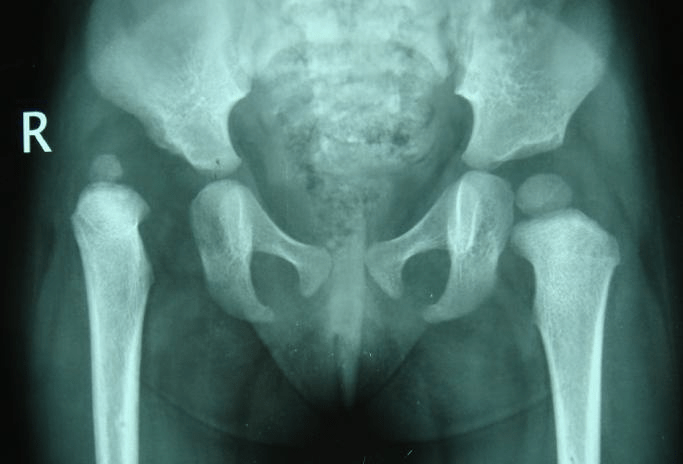

1. 18 months old Pre op & Post-op (OR & Spica)